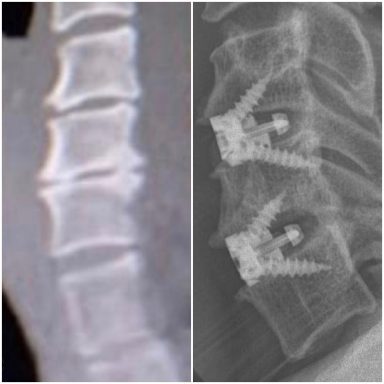

Me detectaron una gran herniación en L4-L5, y bastantes discos desgastados.

Cuando a pesar de la medicación, el deporte, y mi vida saludable, llegó un punto en el que ya no sentía alivio, decidí volver al traumatólogo para comprobar que la hernia no estaba pinzando demasiado la raíz, pero la sorpresa fue que en la RMN, se observaba la existencia bastante evidente de Romanus. Mucho más del que pueda verse en cualquier degeneración vertebral por el paso del tiempo.

En la zona cervical, grandes osteofitos en C5-C6 y C6-C7 posteriores que protuyen en el canal medular produciendo una estenosis foraminal bilateral, y anteriores que protuyen hacia el esófago, por lo que me realizan una artrodesis cervical, quitando todo el osteofito posterior.

Las vértebras L4-L5, totalmente colapsadas, y apófisis transversas impactando en la cresta iliaca, dieron el resultado final de una cojera permanente, por lo que me realizan una artrodesis lumbar con OLIF.